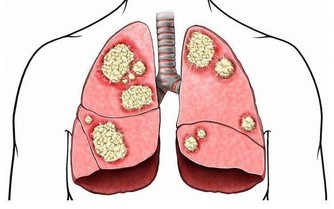

人們對於脂肪肝的常規理解就是大魚大肉比較多,油膩的東西進食太多,不愛運動,不良的生活方式等就成為了危險因素。如果全素食真的就可以和脂肪肝說拜拜了嗎?答案是:錯誤的,因為報導中的男子雖然是全素食飲食,但是絲毫沒有改變飲食中吃主食的習慣,數量反而增加了,這類人群的問題恰恰就出現在這個主食上面。

主食中的澱粉和醣類在滿足機體的需求之後,富裕出來的就會變成脂肪存積起來,如果脂肪過多,就會變成大眾理解的樣子,跑進肝臟裡面,引起脂肪肝。